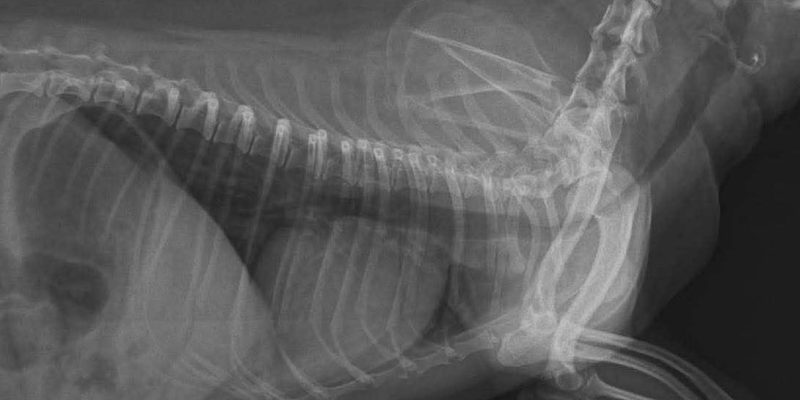

Bệnh nhân đặc biệt của chúng tôi là bé Misa, giống Poodle, 6 năm tuổi, cân nặng 3.3kg. Misa nhập viện trong tình trạng khó thở nghiêm trọng. Sau khi thăm khám và thực hiện các xét nghiệm chuyên sâu, các bác sĩ chẩn đoán bé bị hẹp khí quản nặng kèm theo tình trạng tim to.

Đây là một ca bệnh phức tạp vì sức khỏe của bé vốn đã yếu do biến chứng về tim mạch. Tuy nhiên, với sự quyết tâm của đội ngũ bác sĩ tại ELISA PET, ca phẫu thuật đặt Stent đã được triển khai ngay lập tức để cứu sống bé.

Hẹp hoặc xẹp khí quản là tình trạng các vòng sụn khí quản bị suy yếu, khiến đường thở bị thu hẹp, gây ra các cơn ho kéo dài, khó thở, thậm chí là ngất xỉu do thiếu oxy.